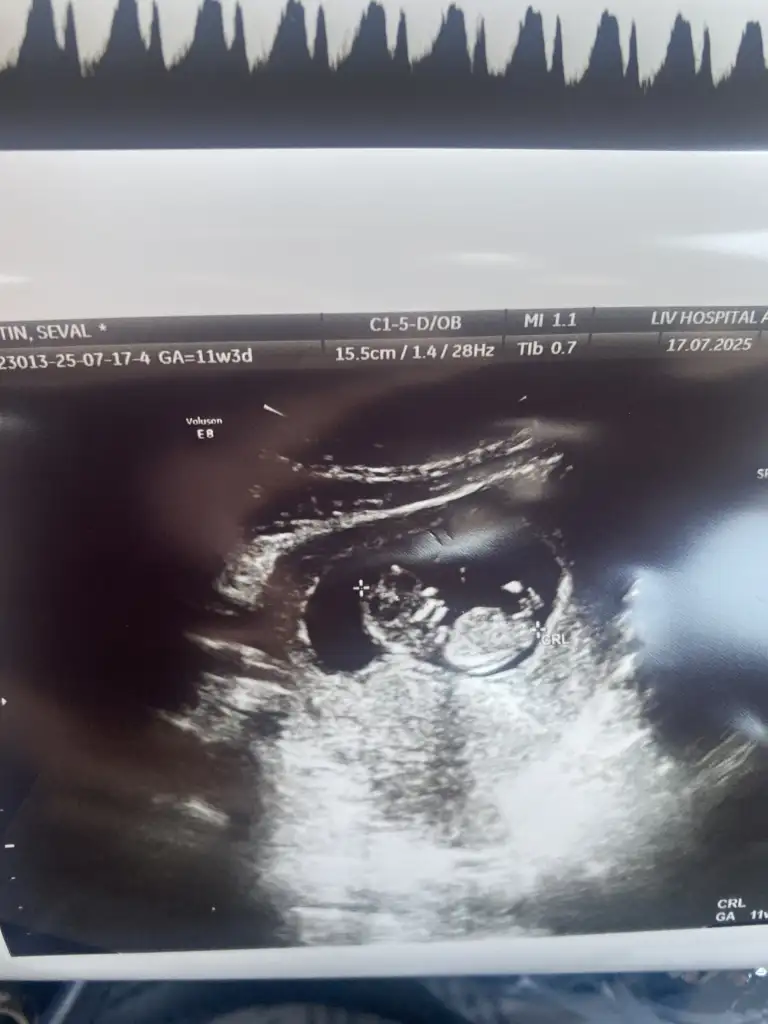

Yorum yaparmısınız. Biri 11hafta 6günlük. Diger 16 haftaKızzzz

kızYorum yaparmısınız. Biri 11hafta 6günlük. Diger 16 hafta

Erkek gibi geldi banaYorum yaparmısınız. Biri 11hafta 6günlük. Diger 16 hafta

Sizinde erkek

Erkek :) givi duruyor ama Allah gönlünüzdekini versinYorum yaparmısınız. Biri 11hafta 6günlük. Diger 16 hafta